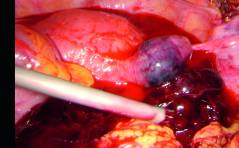

Der Spezielle Fall - Ovarielles Myelom

Eine 41-jährige Patientin stellte sich mit Miktionsbeschwerden in der regulären gynäkologischen Sprechstunde vor. Im transvaginalen Ultraschall konnte eine glatt begrenzte, gut perfundierte, homogene Struktur von 98 × 77 × 87 mm vom linken Ovar ausgehend ... PDF DokumentFHA Persönlich